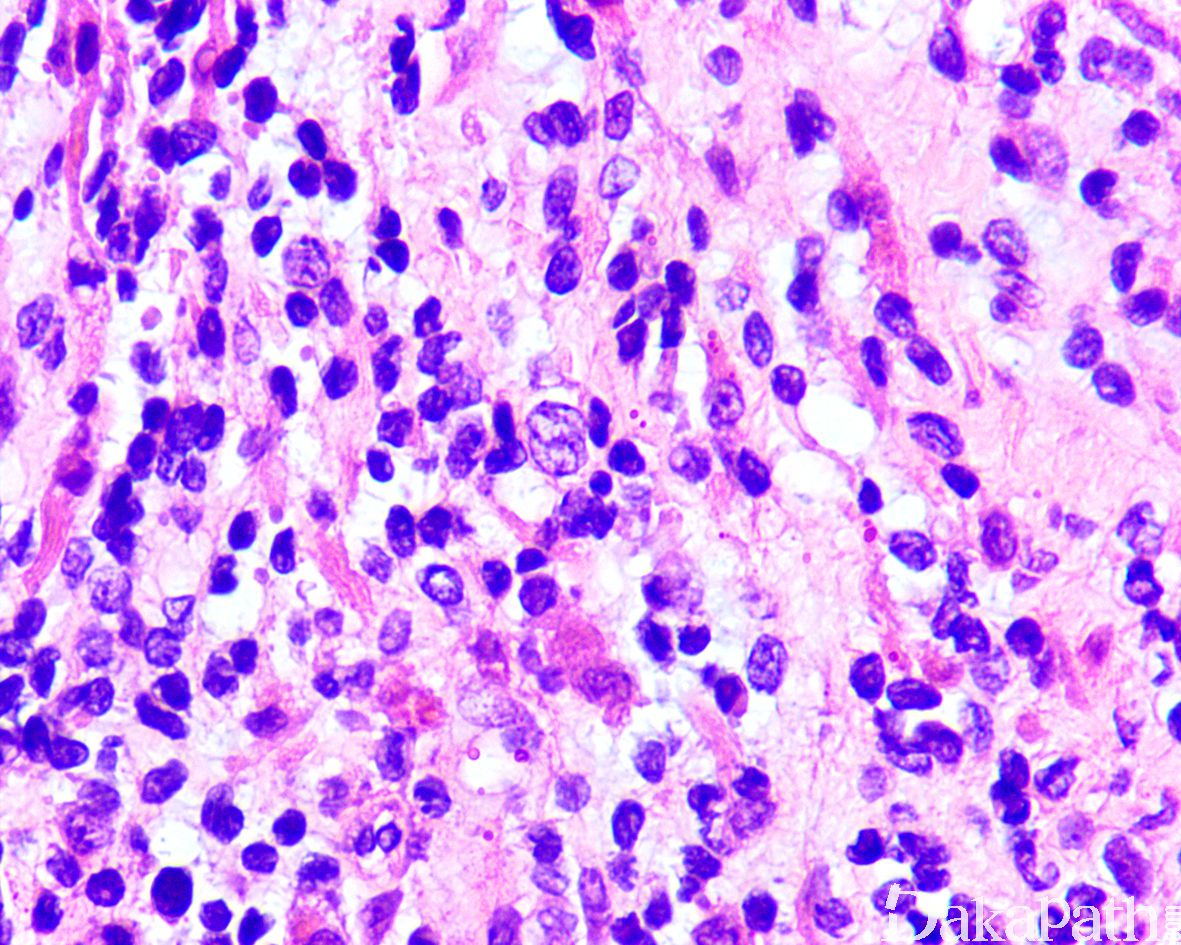

3. 经典型:

4. 瘤细胞排列成片状和巢状而贴附于纤维性间隔上,巢中央瘤细胞黏附性差,相互解离,形成特征性的假腺泡状或微囊状结构;

5. 肿瘤由未分化的原始间叶性细胞及少量早期分化的幼稚横纹肌母细胞组成;

6. 原始间叶性细胞呈圆形、卵圆形或小多边形,胞质少,核深染,核分裂像易见;

7. 腺泡中央的横纹肌母细胞多呈圆形或卵圆形,有时可见到胞质内横纹;

8. 部分病例可见散在的胞质淡染或弱嗜酸性,核位于胞质周边的多核巨细胞;